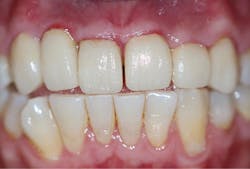

A final impression was made using a base VPS impression material (V-Posil Putty Fast, Voco; figure 11) followed by a light-body VPS impression material wash (V-Posil Light Fast, Voco; figure 12). A provisional crown was made using a cold-cure composite provisional material (Structur 3, Voco; figures 13 and 14) andcemented. The patient was dismissed. Upon return three weeks later, the provisional was removed and the definitive laboratory-fabricated zirconia crown was delivered.

Figure 14: Provisional crown